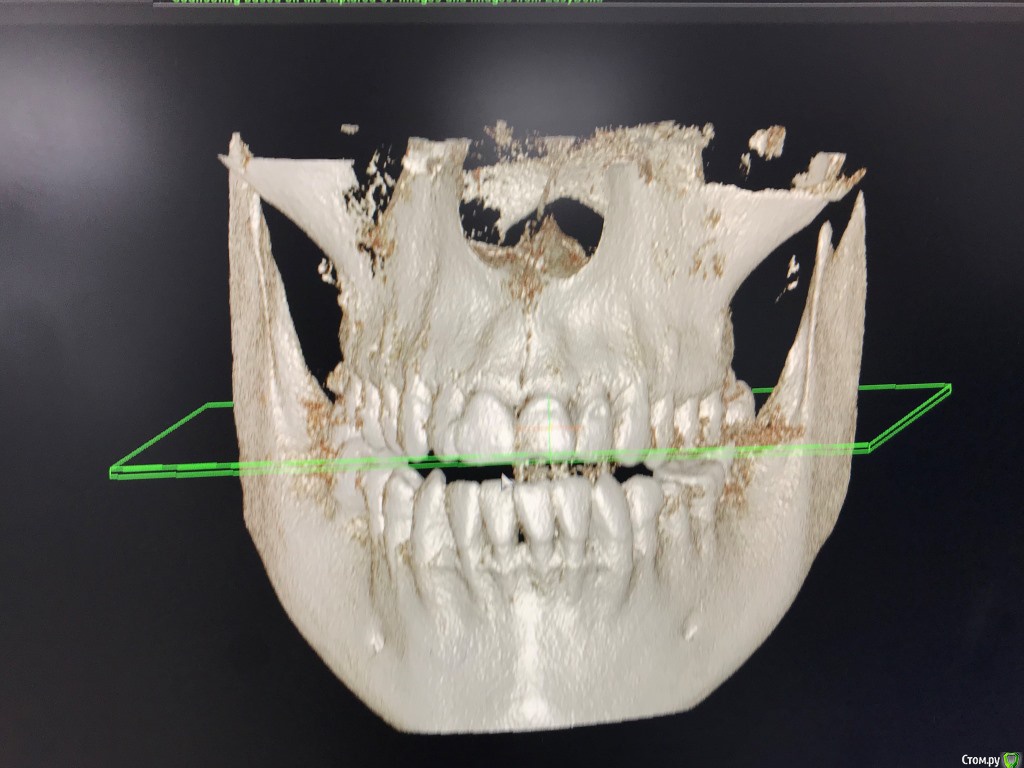

Решилась на исправление прикуса. Была консультация с ортодонтом 15 лет назад, рекомендовали операцию.

Сейчас на паре консультаций противоречивые и неуверенные ответы, может помогут брекеты, может нет.

Хочу понимать нужна ли ЧЛХ. Может сейчас системы позволят сделать прикус правильным без хирургии.

Верхних 8к нет, нижние стоят

6го нижнего нет с 10 лет, в последствии планируется имплантация.